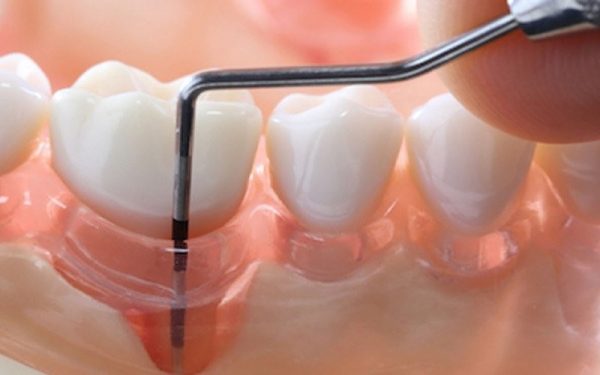

بیماری پریودنتال خفیف مرحله دوم بیماری پریودنتال یا پریودنتیت مزمن، شایع ترین شکل آن است. این شرایط در هر سنی ممکن است رخ دهد اما در بزرگسالان شایع تر است. است. برگشت پذیر نیست، اما قابل مدیریت است. هنگامی که بیمار به این مرحله می رسد، عفونت به استخوان گسترش یافته و روند تخریب استخوان خود را آغاز می کند. مشخصه ویژه آن تشکیل پاکت و تحلیل لثه است. باکتری تکامل می یابد و تهاجمی تر می شود، که باعث از تحلیل بیشتر استخوان می شود. رعایت بهداشت دهان به سادگی دیگر نمی تواند آن را متوقف کند. علائم عبارتند از افزایش تورم یا قرمزی لثه ها، بوی بد دهان، خونریزی حین مسواک زدن یا نخ دندان کشیدن و پروب با عمق بین چهار تا پنج میلی متر.

- جرم گیری: زدودن جرم و باکتری از روی سطح دندان ها و زیر لثه ها. این کار معمولاً حین انجام پاکسازی تخصصی استاندارد دندان ها انجام می شود.

- تسطیح سطح ریشه دندان ها: صاف و صیقلی کردن سطوح ریشه دندان ها برای جلوگیری از انباشته شدن بیشتر جرم و سموم باکتریایی.